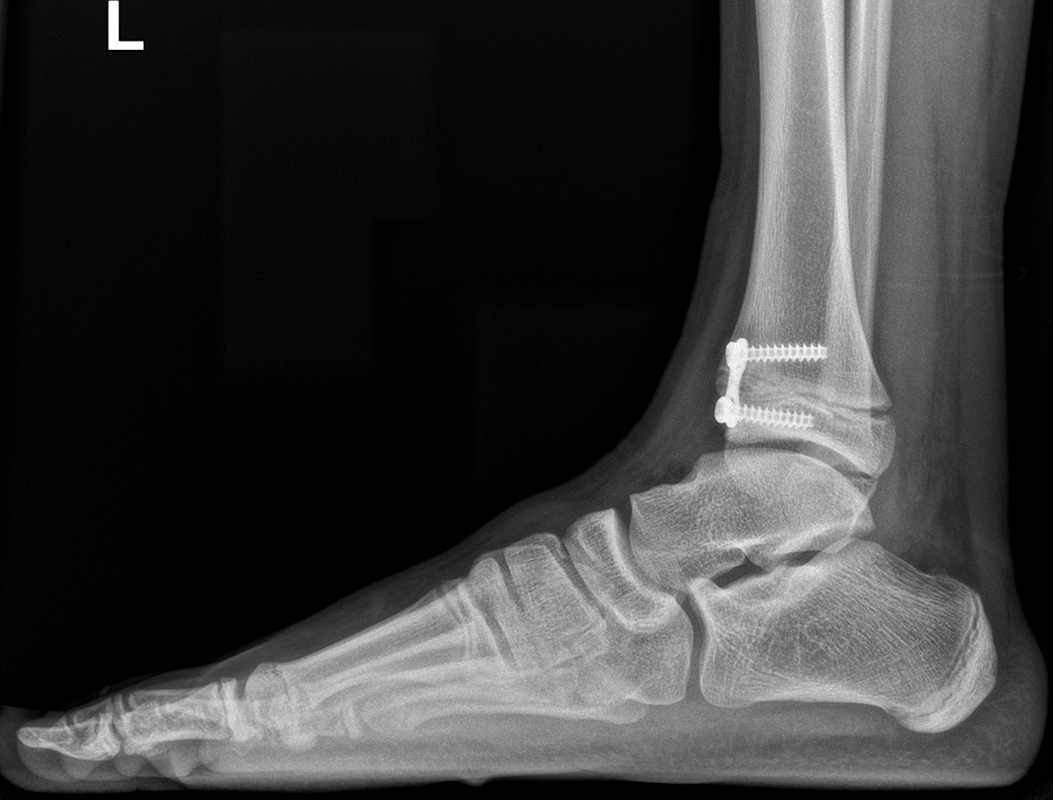

Bei offenen Wachstumsfugen kann über eine Steuerung des Wachstums mit einer Klammer (Blount-Klammer/Flex Tack) oder kleinen Plättchen (Eight Plate) eine Korrektur von Achsabweichungen in der sagittalen und coronaren Ebene erreicht werden (Abb. 8). Der Hautschnitt beträgt ca. 1,5 - 2 cm und die so versorgten Kinder können ihre Extremität direkt postoperativ schmerzadaptiert voll belasten. Die wachstumslenkende Operation mit einer Klammer oder einem Plättchen besitzt ein enormes Korrekturpotential und erspart dem Kind oder Jugendlichen umfangreiche Umstellungsosteotomien und Plattenosteosynthesen, welche eine Schnittlänge von 15 cm und eine Entlastung des operierten Beines von 4-6 Wochen erforderlich machen.

Abb. 8 a-g: Genua vara prä- und postoperativ versorgt mit Flex Tacks (a-b) und ein Genu valgum versorgt mit Eight Plate an der medialen Femurkondyle (c); Spitzfuß bei congenitalem Klumpfuß und einem Flat Top Talus mit präoperativem Röntgenbild seitlich und der deutlich nach dorsal stehender Tibia(d); intraoperative Bilder der Epiphysiodese mittels Eight Plate zur Wachstumslenkung der distalen Tibia in die Extension (e-f) und postoperativer Verlauf nach sechs Monaten mit regelrecht stehender Tibia über dem Talus durch die distale Extension (g).